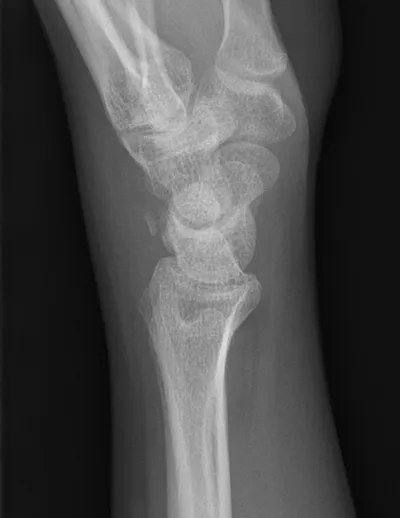

Carpal Radiology Images

This collection contains 1 radiology images related to carpal, including various imaging modalities such as X-rays, MRIs, CT scans, and ultrasound images commonly used in medical diagnosis and education.